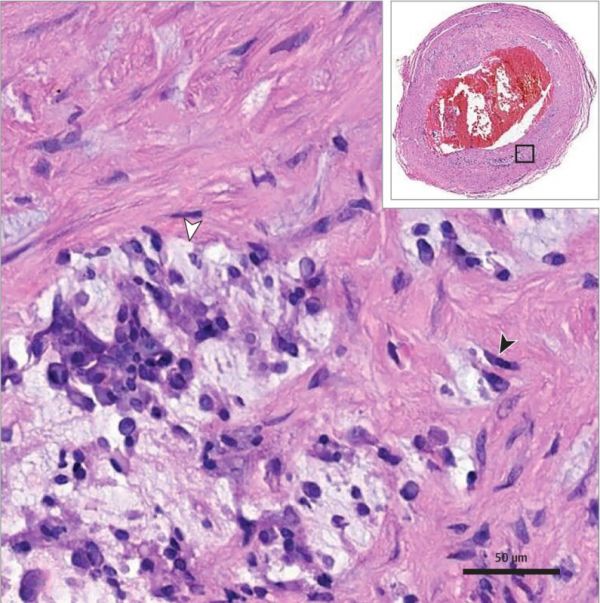

考虑到患者心房黏液瘤的病史,接诊医生还是决定对患者的脊髓进行一次手术。术中发现脊髓萎缩以及一个肿块附着在瘤样扩张的脊髓前动脉表面。病理结果显示:血管外黏液瘤组织,血管腔内黏液瘤样增生(如图)。因此确诊为:心房黏液瘤引起的脊髓梗死和转移。